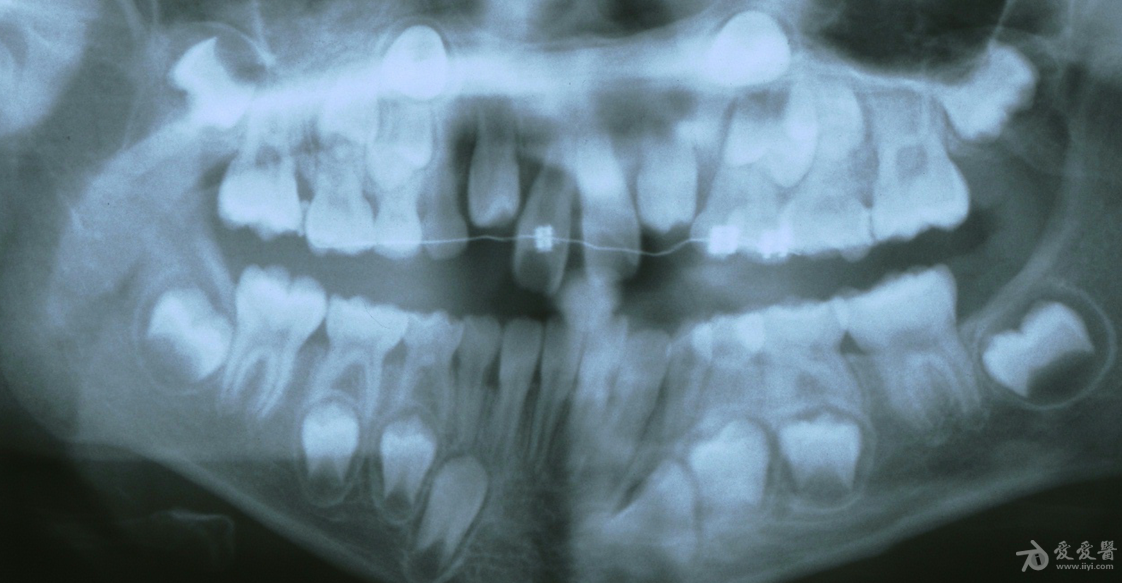

片子显示恒牙胚正在往上顶

(图中显示为颌骨内的恒牙胚)

正常情况下,恒牙胚位于乳牙根的靠近舌头的那一侧,恒牙在萌出过程中